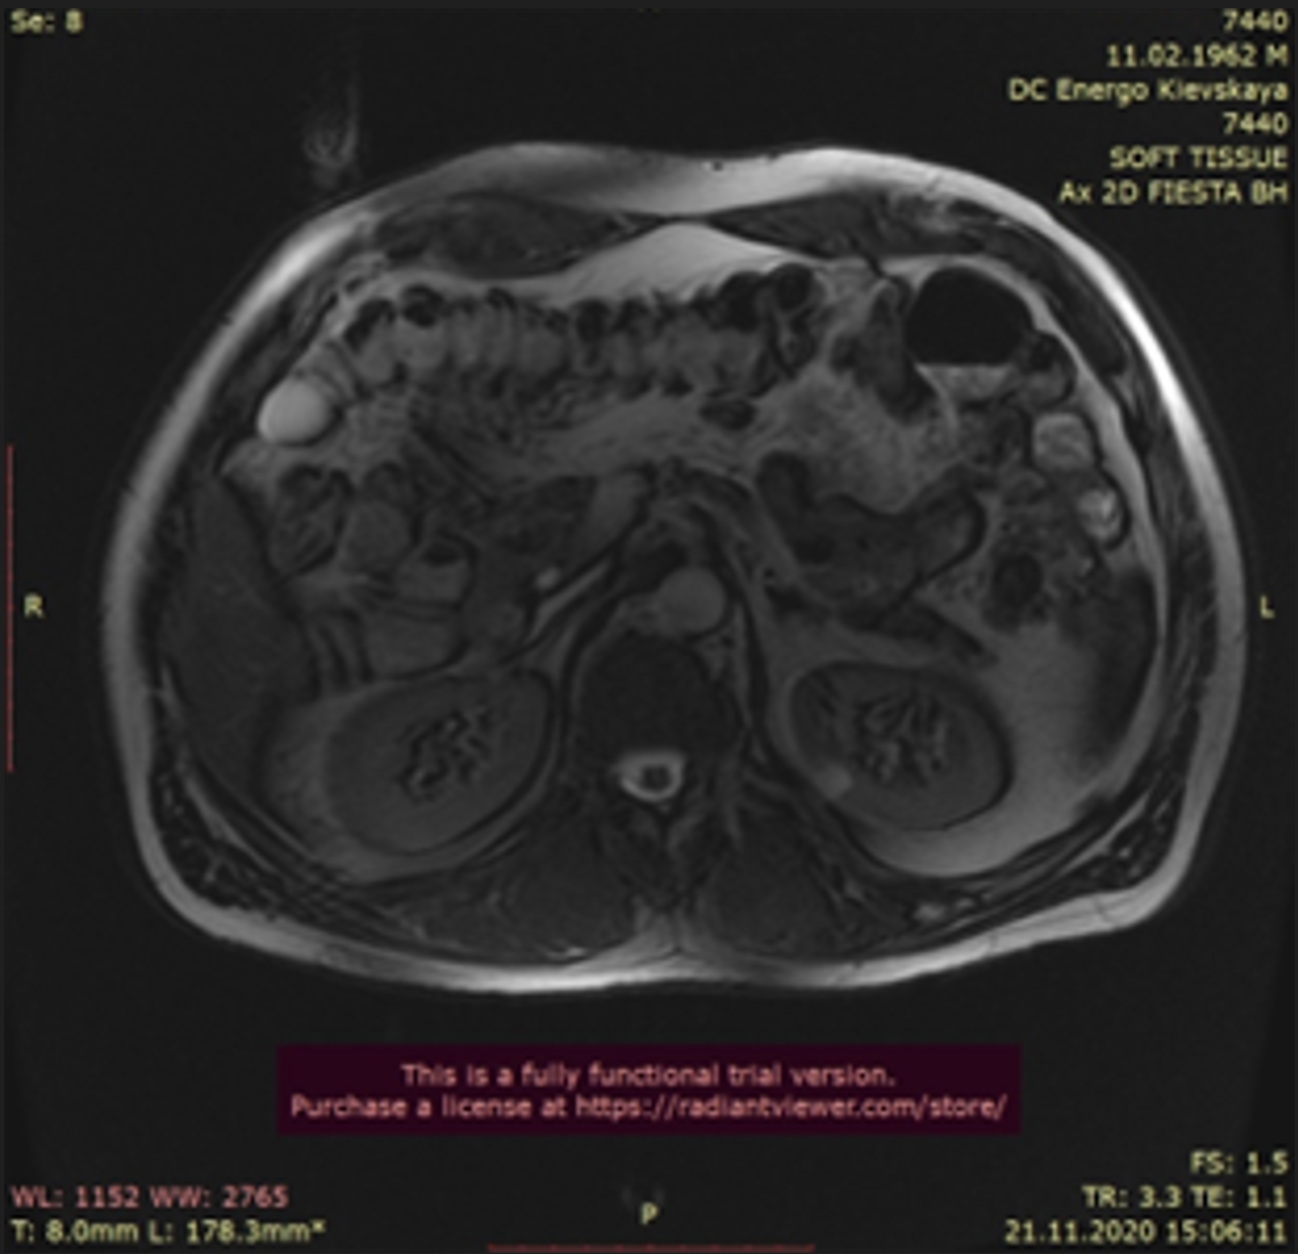

При МРТ (рис.1, 2) брюшной полости под селезеночным изгибом толстой кишки выявляется образование 5 см в диаметре с тонкой равномерной стенкой, горизонтальным уровнем жидкости, сообщающееся с просветом кишки. Визуализируемый участок паретически изменен. Данный участок не изменялся в течение всего исследования. В связи с чем заподозрены: дивертикул тощей кишки (?), инородное тело (?), опухоль (?).

Рис. 1. / Fig. 1.